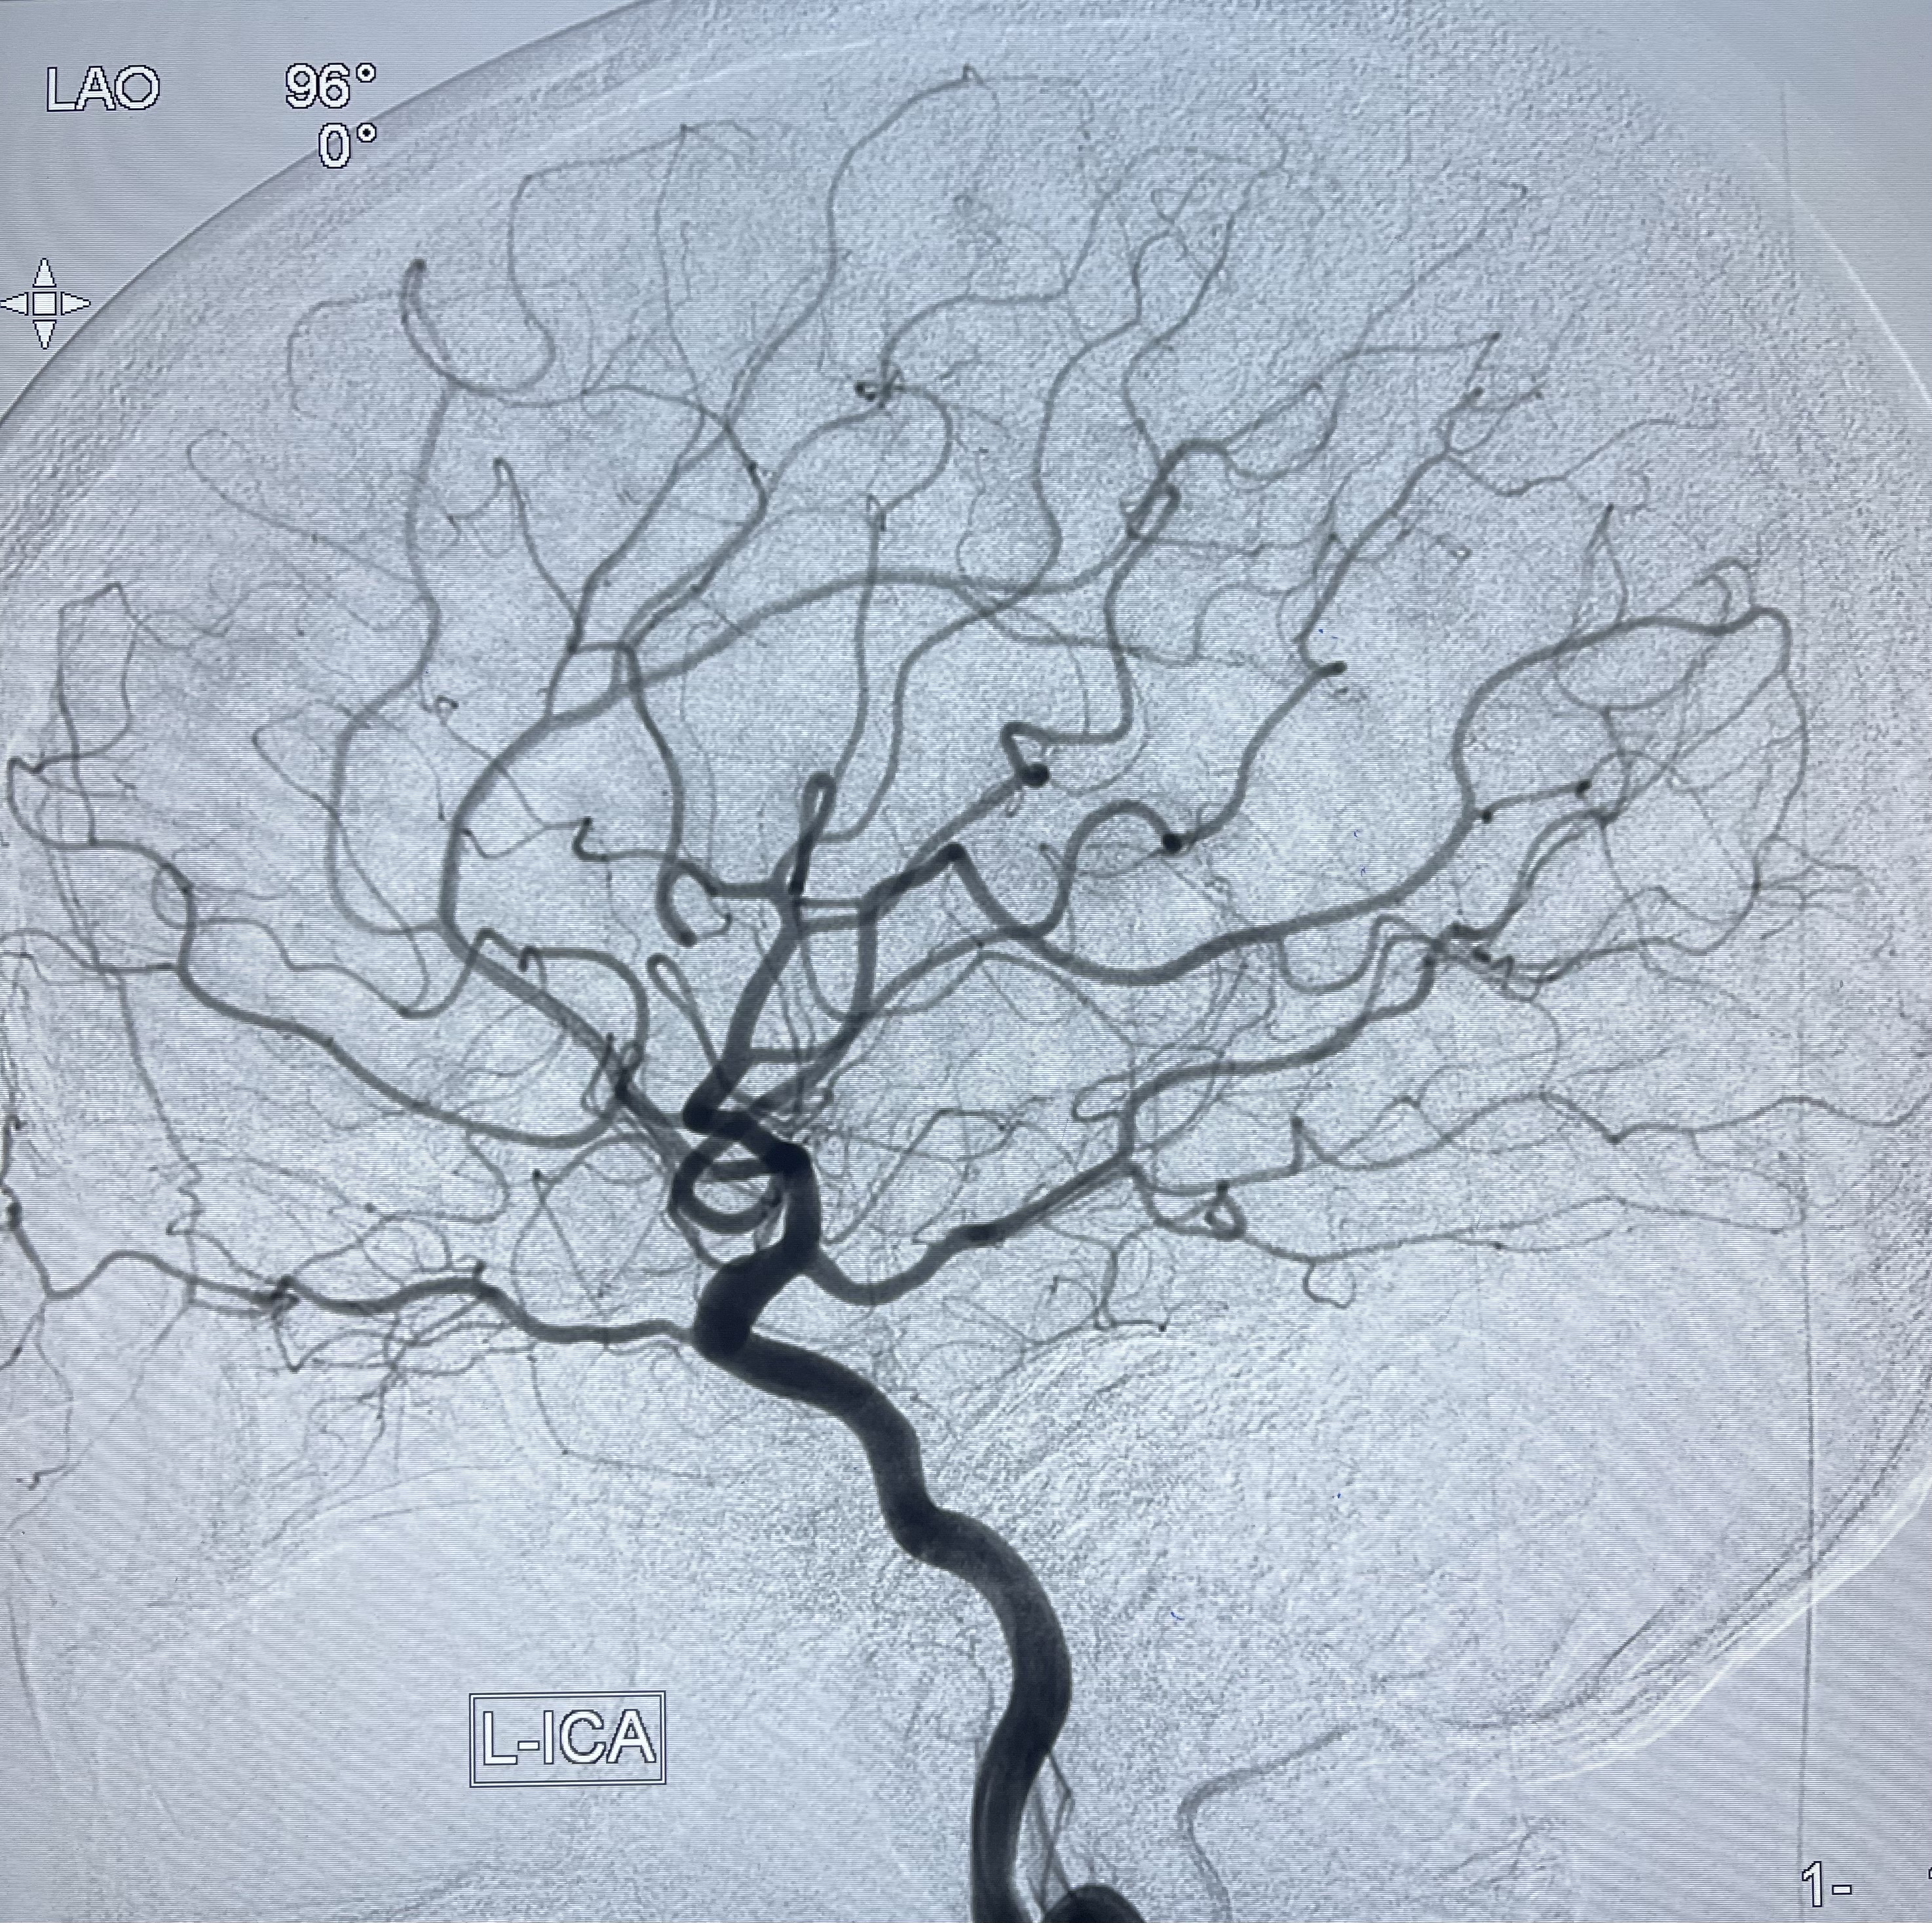

2021-01-07DSA

右侧前交通动脉瘤

箭头所示为左侧A2发出